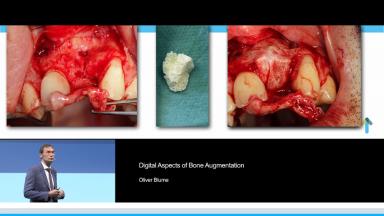

Digital Aspects of Bone Augmentation

The digital world offers us the chance not only to simulate and achieve implant installation along with the prosthetic restoration but also to visualize bone defects and accurately reproduce the missing bone using digital data. As one of the first users of preformed allogenic bone blocks tailored to individual patients, our practice has been able to gather valuable experience over the last five years on the predictability of this augmentation procedure. Using images, videos and animations, the clinical use of allogenic bone blocks produced from CAD/CAM data will be presented. The focus is on the workflow and surgical techniques as well as the presentation of clinical cases and results. The pros and cons, indications as well as the occurrence of complications in regard to this augmentation procedure and how to deal with them will be described.